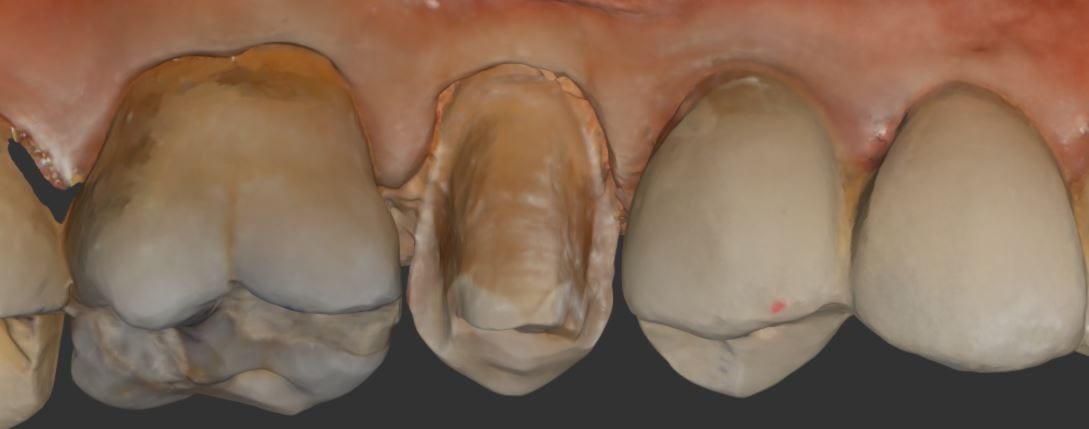

Once the tooth is prepared, the premolar is imaged back into the arch form in high resolution mode. This mode comes in handy for picking up the enamel that is exposed at the cavosurface margins. Some intra-oral imaging systems struggle with picking up the detail in these situations.

You can see how clearly discernible the margins are in this preview. Feel free to download the case data at the end of the article. Please note that areas that are not critical for the restoration design were essentially ignore as they play no significant role in the desired outcome.